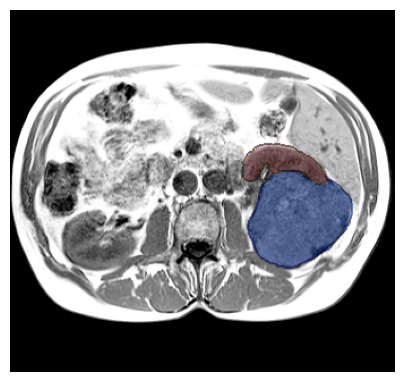

Purpose: To introduce a deep learning model capable of multi-organ segmentation in MRI scans, offering a solution to the current limitations in MRI analysis due to challenges in resolution, standardized intensity values, and variability in sequences. Materials and Methods: he model was trained on 1,200 manually annotated MRI scans from the UK Biobank, 221 in-house MRI scans and 1228 CT scans, leveraging cross-modality transfer learning from CT segmentation models. A human-in-the-loop annotation workflow was employed to efficiently create high-quality segmentations. The model's performance was evaluated on NAKO and the AMOS22 dataset containing 600 and 60 MRI examinations. Dice Similarity Coefficient (DSC) and Hausdorff Distance (HD) was used to assess segmentation accuracy. The model will be open sourced. Results: The model showcased high accuracy in segmenting well-defined organs, achieving Dice Similarity Coefficient (DSC) scores of 0.97 for the right and left lungs, and 0.95 for the heart. It also demonstrated robustness in organs like the liver (DSC: 0.96) and kidneys (DSC: 0.95 left, 0.95 right), which present more variability. However, segmentation of smaller and complex structures such as the portal and splenic veins (DSC: 0.54) and adrenal glands (DSC: 0.65 left, 0.61 right) revealed the need for further model optimization. Conclusion: The proposed model is a robust, tool for accurate segmentation of 40 anatomical structures in MRI and CT images. By leveraging cross-modality learning and interactive annotation, the model achieves strong performance and generalizability across diverse datasets, making it a valuable resource for researchers and clinicians. It is open source and can be downloaded from https://github.com/hhaentze/MRSegmentator.